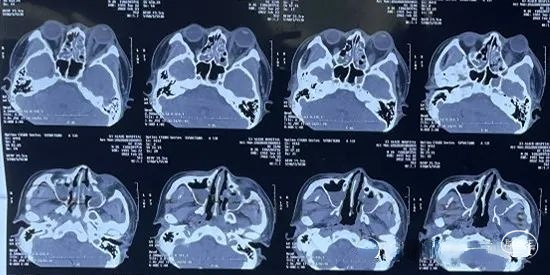

2022.02.05MR:鼻腔,眼眶内感染范围继续扩大,额叶脑组织水肿明显,但并无脓肿形成。

2022.02.07 MR:鼻腔,眼眶内呈现术后改变,额叶水肿范围逐渐局限。